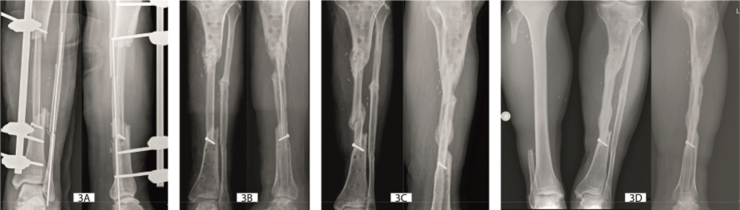

Results: When bony consolidation of the 33 cases were examined in detail, 4 different modes of flap hypertrophy were defined: type 0- absence of hypertrophy, type 1- limited hypertrophy, type 2- marked hypertrophy triggered by stress fracture, and type 3- massive hypertrophy enhanced by peripheral bone production.